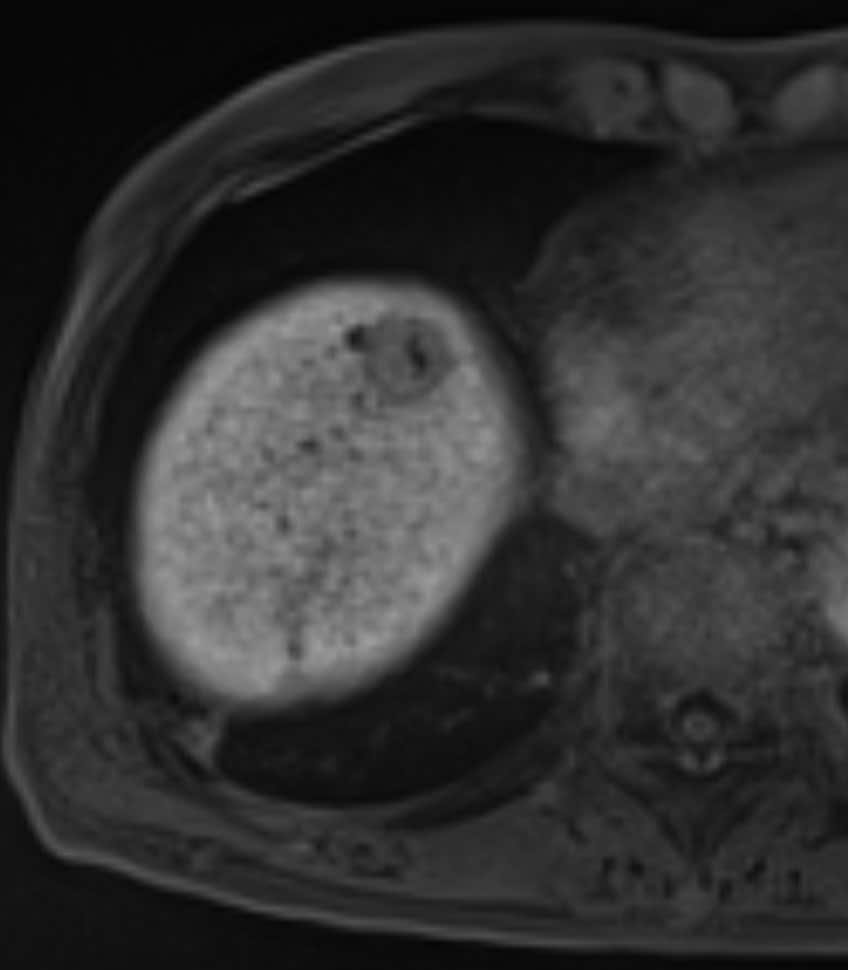

60歳代、女性、53kg、HCC

C型肝炎でフォロー中に肝腫瘍の指摘あり。前医CTにて肝内胆管癌が疑われ、手術目的に当院紹介。肝腫瘍の術前精査目的に再度造影CTとEOB-MRIを施行した。

Necrotic HCCと診断され、切除術を施行された。病理診断でも No residual carcinoma with necrosisとの診断であった。その後再発を認めず、経過観察となっている。

C型肝炎でフォロー中に出現した肝腫瘤について、前医CTではiCCが疑われたが、EOB-MRIにてNecrotic HCCが疑われた。肝切除を施行し、病理学的にもNecrotic HCCが証明された。EOB-MRIは,肝腫瘍の質的診断において有用であることが、あらためて確認された。